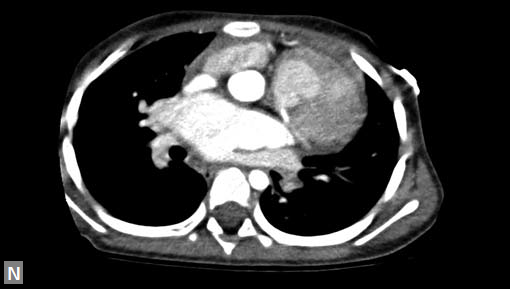

Any part of aorta can get affected by aneurysms. Focal

dilations can be saccular or fusiform. Atherosclerosis is

the most common cause. Tubercular and other infective

aneurysms, traumatic ones are also uncommonly seen. Size

of the aneurysm, proximity to origin of main vessels, relation

with branching and bifurcation, presence of mural thrombus

are the critical information sought on CT.

Contained leak, rupture are the feared complications.

Aortoenteric fistula is a rare but potentially catastrophic

complication. Aneurysmal dilation is common in ascending

aorta (Figs 19W to Y).

CT is also useful in surveillance of diagnosed aneurysms.

Figs 19A to Y (A to C) Scannogram (A), plain (B) and contrast study (C) show partial anomalous pulmonary venous connection; (D to F) Heterotaxy; (G) Aortic occlusion; (H and I) Aortic stents; (J) Aortic dissection with ‘Benz’ sign due to second dissection within the true lumen; (K, L and M) Aortic dissection with thrombus in pseudolumen following catheter angiogram; (N) Aortic dissection involving common carotid arteries and subclavian artery; (O, P, Q and R) Aortic dissection with right renal artery arising from true lumen and left renal artery from false lumen; (S, T, U and V) Stanford B dissection with extension Y to iliac vessels; (W to Y) Aneurysmal dilation of ascending aorta